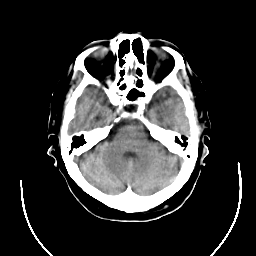

CT Study #3 -- Slice #8

[Home][Help][Clinical][Tour 1] Slice 8